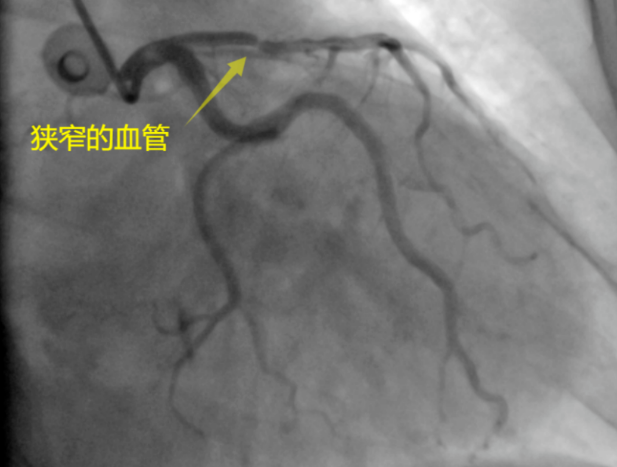

之后,大妈在燕化医院心内科进行了冠状动脉造影检查,发现她的三根冠状动脉中,有一根已经堵塞了95%。李钢主任亲自上阵,顺利地为大妈植入了“BioFreedom无聚合物载体药物涂层支架”。至此,笼罩在大妈一家困扰如风中的薄雾一般烟消云散了。